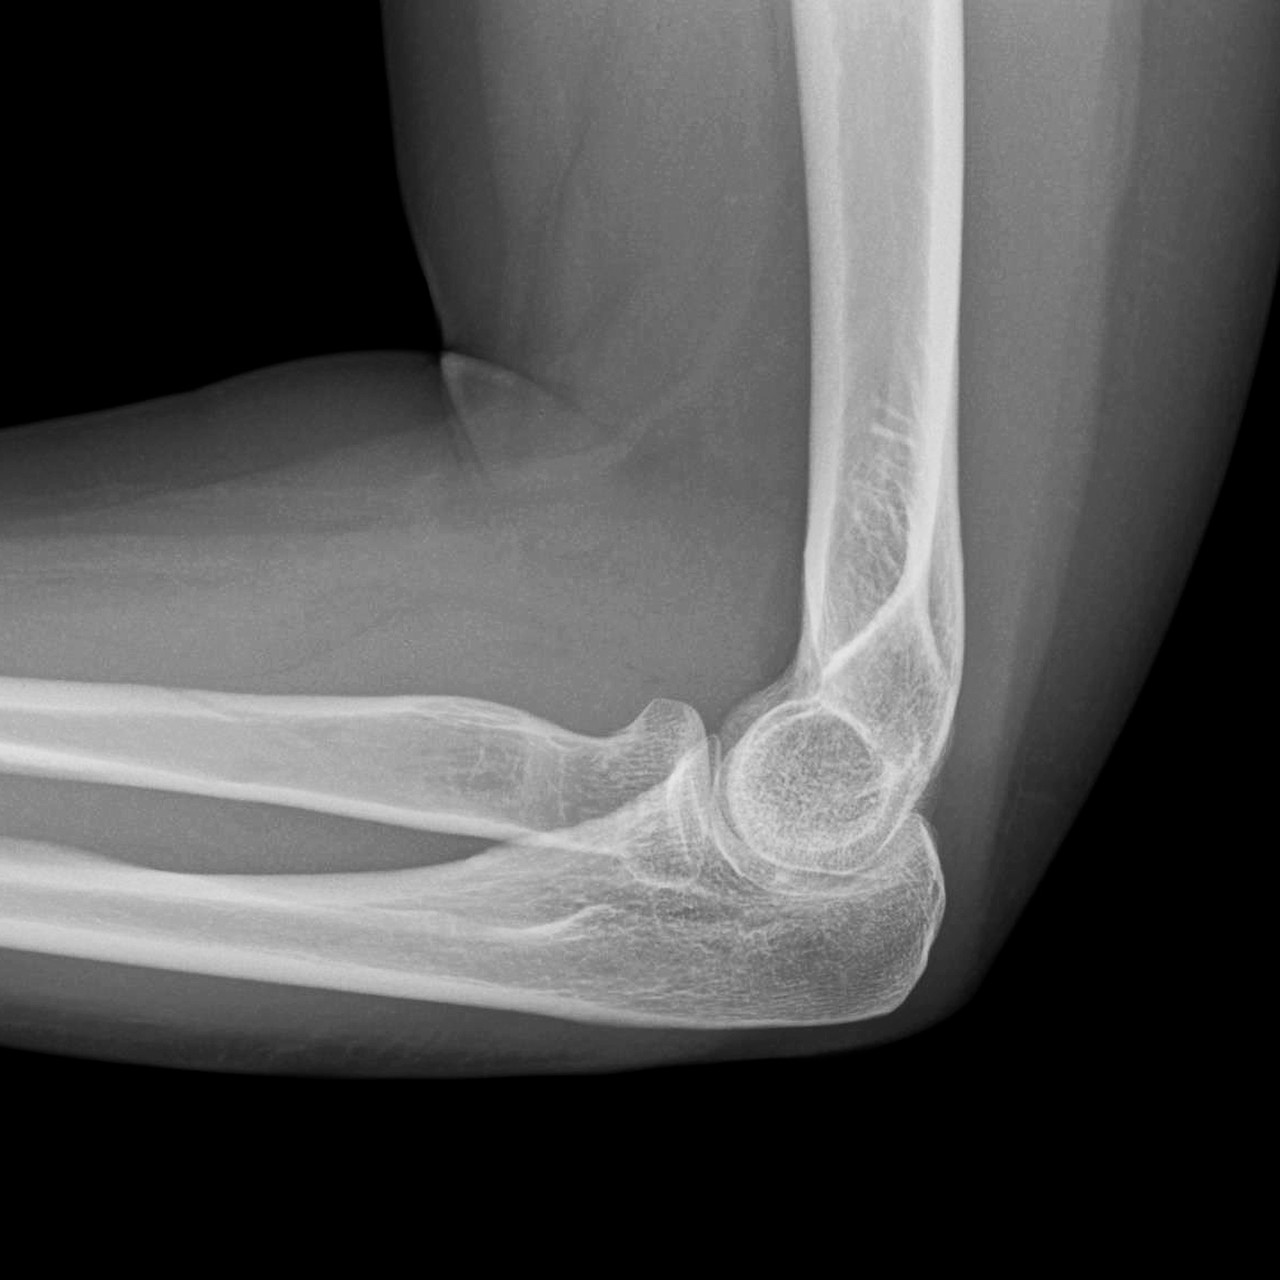

영상의학 검사

서울퍼펙트정형외과의 영상의학 검사는 먼저 방사선검사로 확인하여 석회나 다른 질환으로 인한 통증은 아닌지를 확인합니다. 팔꿈치 상과염은 대부분 간단한 초음파검사로 진단 가능합니다.

영상의학검사